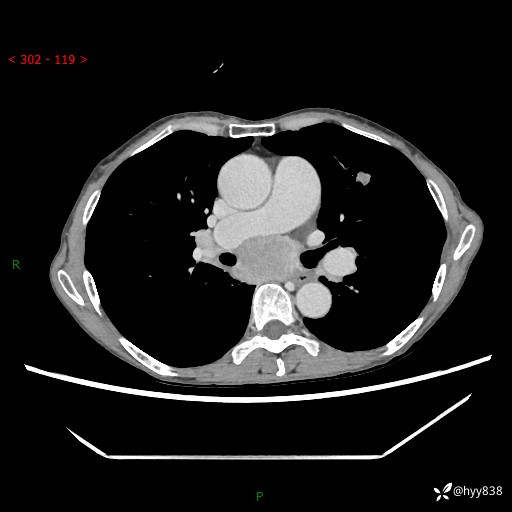

69岁/女,发现肺占位3天余。精彩好病例,请慧诊---(有结果)

【患者信息】:69岁/女

【主诉】:发现肺占位3天余

【现病史及既往史】:患者3天余前因既往肺气肿复查胸部CT发现“右肺下叶结节、双肺多发结节、双肺门及纵膈淋巴结增大”,平素偶有咳白色粘液痰,下肢乏力,无明显低热、盗汗、咯血、胸痛、喘气等不适,今为求明显结节性质遂来我院门诊就诊,门诊以“孤立性肺结节”收治入院。 起病以来,患者精神饮食睡眠一般,大小便正常,体力无明细变化,体重近年来较前下降。

【检查】:胸部CT增强